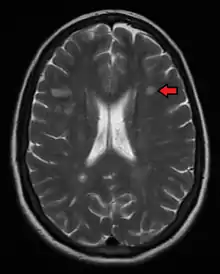

Magnetic resonance imaging (MRI) of the brain and spine may show areas of demyelination (lesions or plaques). Gadolinium can be administered intravenously as a contrast agent to highlight active plaques, and by elimination, demonstrate the existence of historical lesions not associated with symptoms at the moment of the evaluation.[83][84]

Central vein signs (CVSs) have been proposed as a good indicator of MS in comparison with other conditions causing white lesions.[85][86][87][88] One small study found fewer CVSs in older and hypertensive people.[89] Further research on CVS as a biomarker for MS is ongoing.[90]